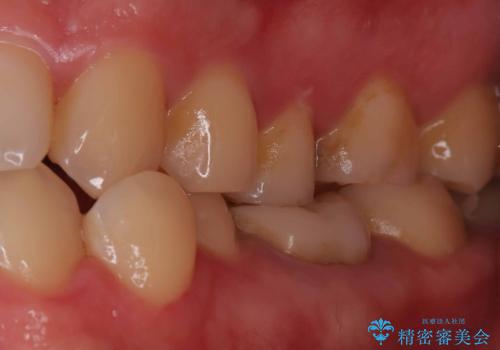

- 定期検診で虫歯が見つかった患者様です。ハイブリッドインレーで治療を行いました。

定期検診で虫歯が見つかった患者様です。

ハイブリッドインレーで治療を行いました。

ハイブリッドインレーはセラミックインレーとは違い、セラミックとプラスチックの混合物です。保険治療の材料よりは優れていますが、プラスチックが混ざっている分、セラミックインレーには劣ります。型取りの材料はセラミックインレーの時と同様のシリコン印象材を使用しています。